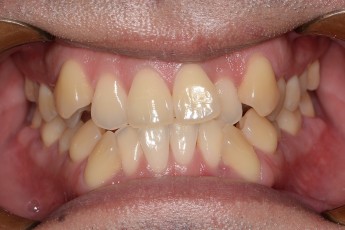

BEFORE & AFTER

- 덧니교정